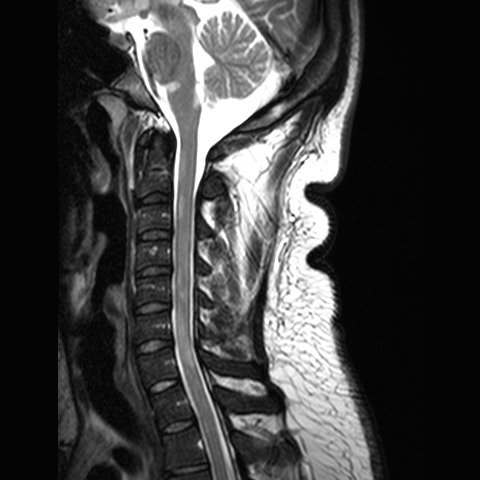

Widespread use of MRI (magnetic resonance imaging) has revolutionized the ability to diagnose multiple sclerosis. Disease-related changes in the brain or spinal cord are detected by MRI in more than 90% of people suspected of having MS.

MRI can often detect damaged areas in the brain or spinal cord that would be missed by other imaging techniques such as a CAT scan.

• To detect MS. MRI is considered the best test to help diagnose MS. However, 5% of people with MS do not have abnormalities detected on MRI; thus, a “negative” scan does not completely rule out MS. In addition, some common changes of aging may look like MS on a MRI.